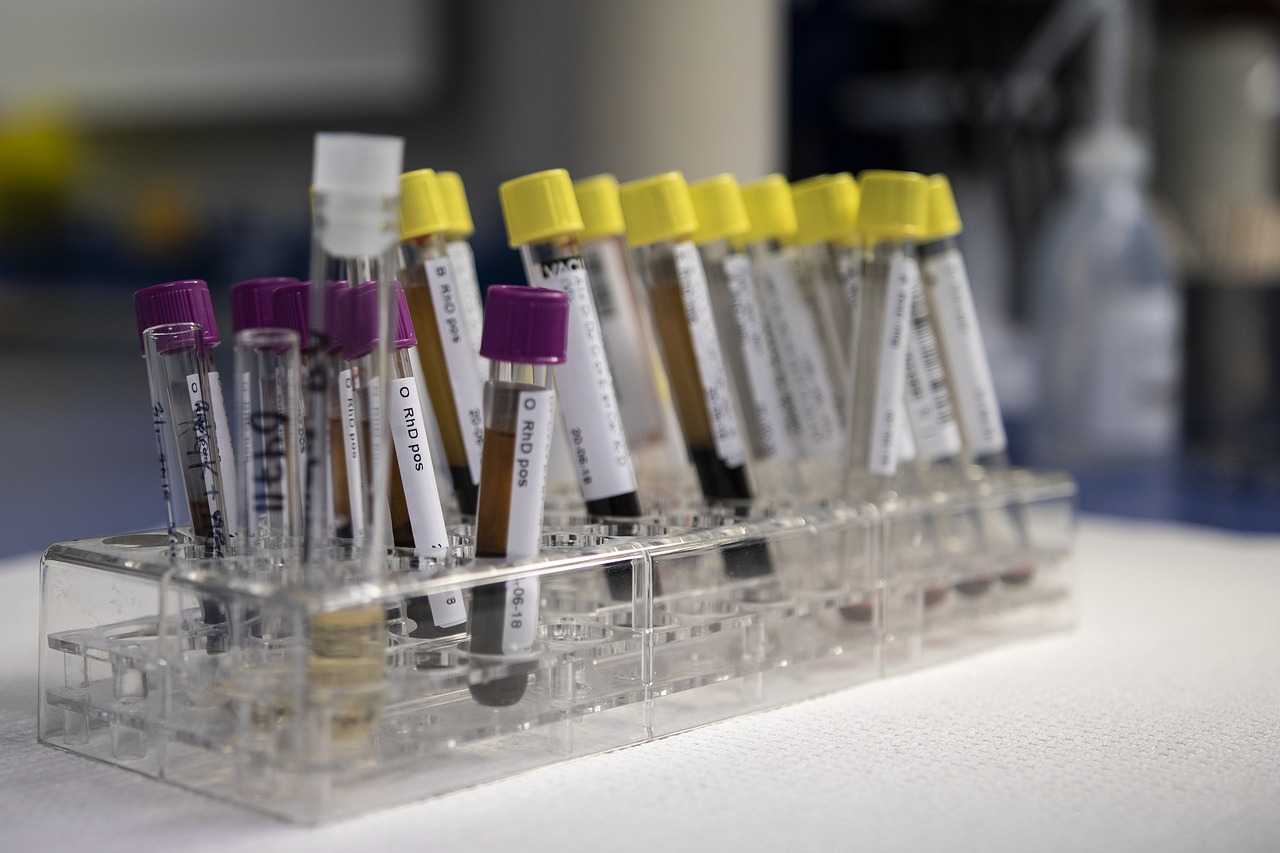

Ogni gravidanza inizia con un test delle urine positivo, quel test, attesta infatti la presenza dell’ormone Beta Hcg nelle urine, sintomo che una gravidanza si sta instaurando. Da quel primo test rapido, che si può trovare facilmente in qualsiasi farmacia o supermercato, susseguono di norma le analisi del sangue per testare la presenza e il dosaggio di questo ormone nel sangue.

Attraverso questo test, si può individuare in modo quasi preciso la settimana di gravidanza che si sta affrontando e, a differenza degli test di gravidanza sulle urine, che una donna esegue sempre a seguito di un ritardo delle mestruazioni, il test sul sangue può essere un modo per avere una diagnosi di gravidanza precoce, se eseguito qualche giorno prima della data delle previste mestruazioni. Scopriamo cosa è l’ormone Beta Hcg, perché si misura, quali sono i dosaggi in gravidanza e come dovrebbe raddoppiare nelle prime settimane.

La quantità di Beta Hcg che il corpo produce può essere considerato un marcatore della gravidanza, che può essere rilevato attraverso il test sulle urine e sul sangue, quest’ultimo quello più sensibile e preciso al rilevamento della gonatropina corionica umana.